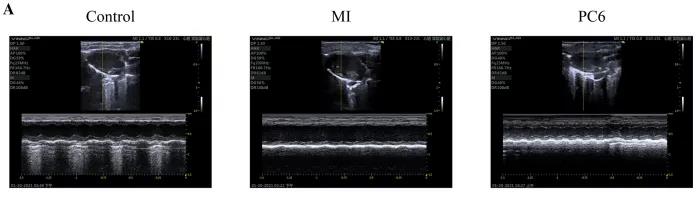

成年雄性C57BL/6雄性小鼠隨機(jī)分為對(duì)照組、MI組和PC6組。MI組小鼠為通過(guò)結(jié)扎冠狀動(dòng)脈左前降支(LAD)形成MI模型,PC6組在造模完成后,針刺內(nèi)關(guān)穴治療5天后取材。經(jīng)胸超聲心動(dòng)圖評(píng)估MI手術(shù)前后小鼠心功能情況,并進(jìn)行血清心肌酶和炎癥細(xì)胞因子的測(cè)定,之后三組樣本各取3個(gè)重復(fù),共9個(gè)樣本進(jìn)行ONT全長(zhǎng)轉(zhuǎn)錄組測(cè)序。

為了探討針刺PC6穴對(duì)心肌損傷的影響,作者首先評(píng)估了心功能和梗死面積。超聲心動(dòng)圖結(jié)果顯示MI組的EF(ejection fraction)和FS(fractional shortening)均較對(duì)照組明顯降低。PC6穴位治療后,EF和FS均增加。針刺治療5天后, 采用TTC染色檢測(cè)梗死面積。結(jié)果顯示,針刺治療顯著減小心肌損傷的大小。采用ELISA法測(cè)定反映急性心肌損傷的心肌特異性血清酶,包括心肌肌鈣蛋白T (cTnT)和心肌肌鈣蛋白I (cTnI)的水平。結(jié)果表明,心肌梗死術(shù)后cTnT和cTnI水平升高,針刺可顯著降低血清酶水平。